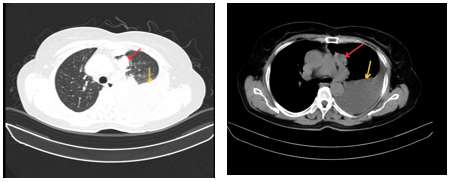

-         Cộng hưởng từ sọ não: Nhu mô bán cầu tiểu não trái và thuỳ đỉnh trái cạnh thể trai có tổn thương tăng tín hiệu trên FLAIR, ngấm thuốc viền sau tiêm, phù não rộng xung quanh, kích thước 11x12mm và 7mm (theo dõi thứ phát). Nhu mô chất trắng cạnh não thất bên và trung tâm bán bầu dục hai bên có vài nốt thoái hoá myelin chất trắng, đường kính <5mm

Hình 2: Cộng hưởng từ sọ não lúc mới nhập viện: Tổn thương tăng tín hiệu trên FLAIR tại bán cầu tiểu não trái và thùy đỉnh trái cạnh não thất (mũi tên đỏ).